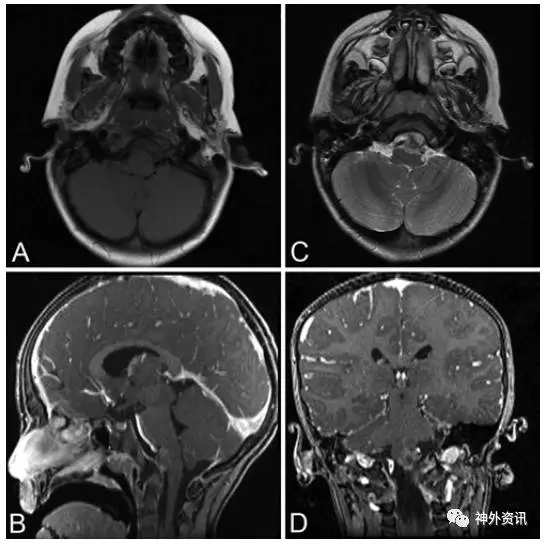

5岁男性患儿,诊断为斜坡脊索瘤(图1)。5年前行经口入路完全切除肿瘤(图2),术后进行质子束放疗。病理学检查报告为典型的脊索瘤,免疫组化提示角蛋白强阳性、上皮膜抗原强阳性、S-100免疫反应阴性和MIB-1标记指数为10%(图3)。术后因脑脊液漏反复出现脑膜炎,给予抗生素治疗后好转。接着继发交通性脑积水,通过脑脊液VP分流术降颅内压。术后5年发现肺部结节(图4),手术活检提示为低分化的脊索瘤,免疫组化结果和原发部位脊索瘤相似,即角蛋白强阳性和上皮膜抗原强阳性(图5),表明斜坡脊索瘤颅外转移。随后相继发生胸壁和颅骨转移。由于大部分脊索瘤mTOR通路激活,所以给患者使用伊马替尼联合雷帕霉素化疗后,肿瘤缩小,疼痛有所减轻。但是,9月后出现额部头皮肿物,并导致附近的VP分流管周围皮肤破溃。遂行头皮肿物切除和皮瓣转移术,以防止分流管暴露。免疫组化提示PD-L1高表达,即行PD-L1单抗治疗,胸痛明显缓解。6月后又出现新发的肺部转移灶,疼痛明显。免疫组化和基因检测为INI-1缺失,应用EZH2进行晚期解救治疗,疗效尚待评价。

图1. MRI提示斜坡区一肿物。A.TI加权平扫;C.T2加权平扫;B和D.T1加权增强。